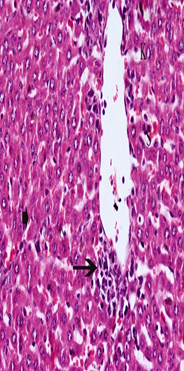

Ginger+Cisplatintreatment attenuated the cisplatin induced liver tissue injury, with inflammatory cells, congestion central vein, blood sinusoids and pyknotic nuclei were observed (fig. 8). However, the pathological hepatic lesions induced by cisplatin were remarkably ameliorated by Ginger+Cisplatin+Sodium salicylate nanodrug except few inflammatory cells and congestion blood sinusoids (fig. 9).

Fig. 8: It shows photomicrograph of section from liver of Ginger+Cisplatin (H and E X 400)

Fig. 9: It shows photomicrograph of section from liver of Ginger+Cisplatin+Sodium salicylate (H and E X 400)